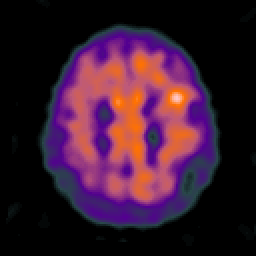

Alzheimer's disease: overlay -- Slice #19

[Home][Help][Clinical] Slice 19